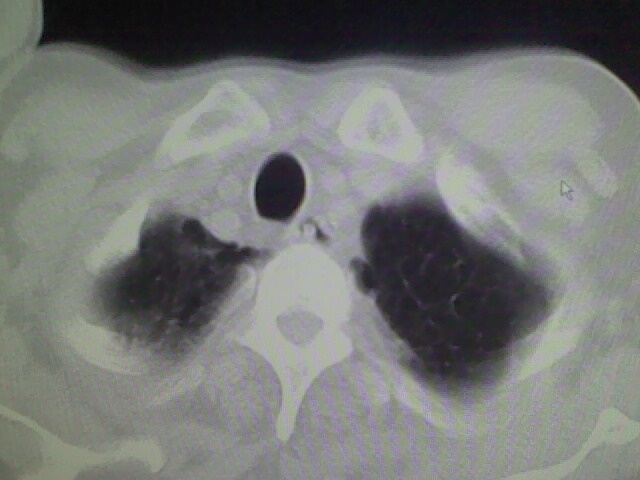

男,70岁,脑出血,长期卧床,左侧背部可触及肿块

慢性间质性炎症,与老年患者长期卧床相关,胸壁软组织及肋骨未见异常。

考虑右肺及左肺下叶炎症。

右肺及左肺下叶炎症。

右肺肺气肿并炎症。

肺气肿并炎症。